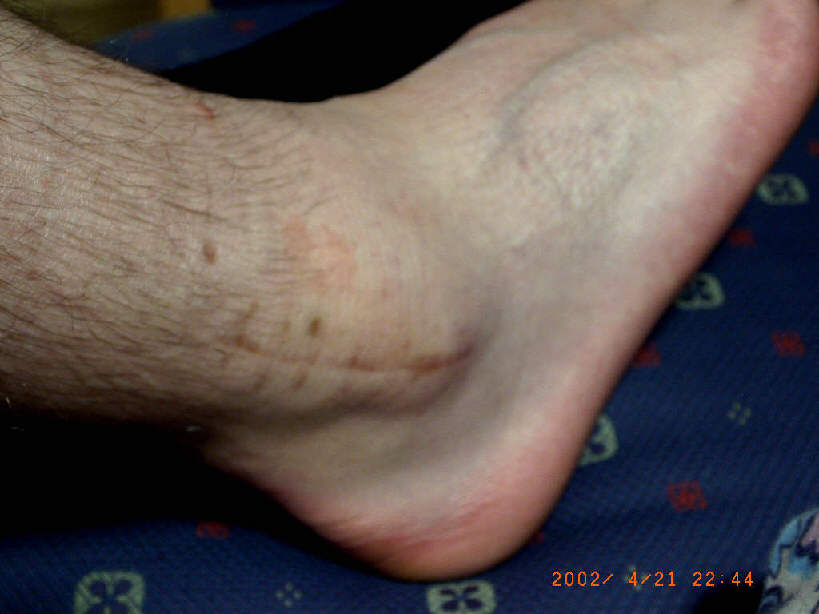

Am 23.04.2002 bin ich das Material aus meinem Knöchel losgeworden !!

Ich war wieder in der Berufsgenossenschaftlichen Unfallklinik in Frankurt am Main.

R0011569hp_index

R0011572hp_index

R0011584hp_index

R0011588hp_index